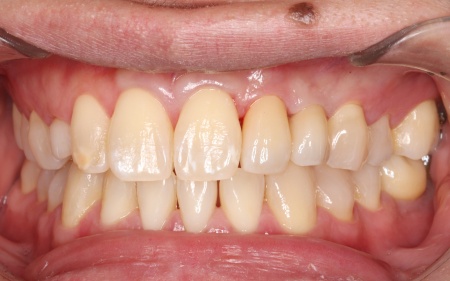

②失った歯の手前の前歯1本を支えとして、2本分の被せ物を装着する片側固定ブリッジ

メリット:外科的な処置を行わずに歯を補える。一般的なブリッジでは前後の歯を削る必要があるものの、今回は手前の歯のみを土台とするため、削る歯の本数を最小限に抑えられる

デメリット:支えとなる手前の歯をひとまわり小さく削る必要がある

それぞれのメリット・デメリットをご説明したところ、患者様は当初①のインプラント治療をご希望でしたが、矯正治療の併用や治療期間の長さへの不安から、最終的に②の片側固定ブリッジを選択されました。

また今回はブリッジを装着するためのスペースがやや不足しているため、手前の歯を小さめに削って必要なスペースを確保する必要があることも併せて説明しています。

被せ物の素材は患者様と相談のうえ、自然な白さがあり変色や劣化が起こりにくいセラミックを選択しました。